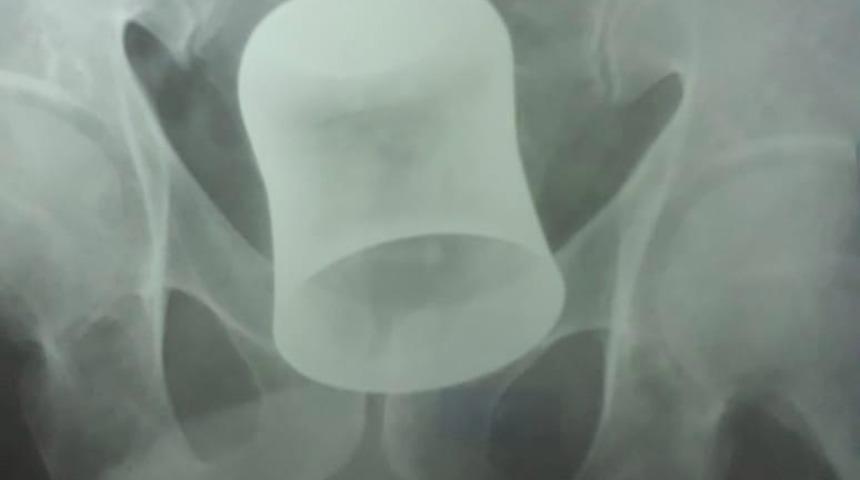

İlk tetkiklerin ardından doktorlar şoke oldu. Zira adamın bağırsaklarında metal bir bardak olduğunu fark ettiler.

10 gündür içinde metal bir bardakla yaşayan adam ameliyata alındı.

Doktorlar önce makattan ameliyata başladıklarını ancak başarılı olamayınca bardağı mideden girerek çıkardıklarını söylediler.